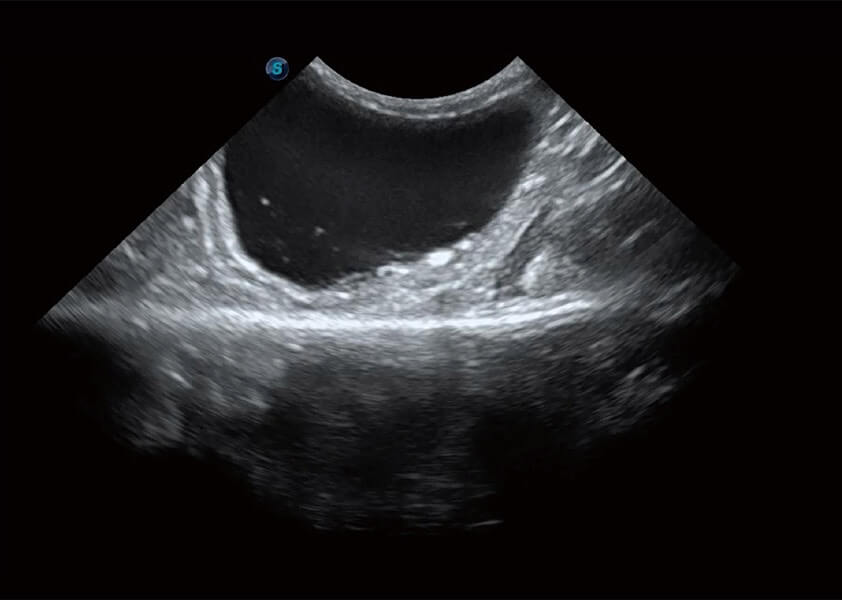

ProPet 60 作为一款高端台式动物超声设备,为动物医生的日常诊断提供了一系列贴合动物临床需求、解决临床实际问题的高级成像功能。凭借全系列高清探头,满足医生对腹部、心脏、生殖、浅表、肌骨等成像的所有需求,切实帮助您提升检查效率,提高诊断信心。

兽用彩色多普勒超声诊断系统

动物是人类最亲密的朋友和最值得信赖的伙伴。美狮贵宾会官网也一直致力于探索动物专用的超声影像解决方案。 全新推出的ProPet系列,是美狮贵宾会官网在动物超声影像智能化、专业化、精准化的一次跨越式革新。动物不能用言语来表述自己的不适,通过超声影像,ProPet系列搭建了动物医生与不同物种沟通的“桥梁”,为动物医生注入了“治愈之力”。